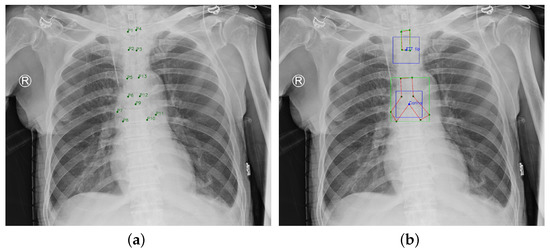

This paper was approved by the institutional review board (IRB) of the National Cheng Kung University (NCKU) Hospital (IRB number: A-ER-108-305). The chest radiograph dataset provided by NCKU Hospital includes 1,870 portable chest radiographs of intubated ICU patients in DICOM format and the ground truth (GT) annotations were labeled by two board-certified intensivists. The GT ETT was labelled by four points ( P 1 4 ), and the GT tracheal bifurcation was labelled by nine points ( P 5 13 ), as shown in Figure 6a. The purpose of this paper was to detect the malposition by locating the ETT tip and the Carina. Therefore, this paper adopted two boxes with a size of 300 × 300 to label the feature point of the ETT tip which was the middle point of P 2 and P 3 , and the feature point of the Carina which was P 9 (the feature point of ETT tip and Carina are at the center of the boxes). Furthermore, the 13 points were corrected to be sequential for generating the GT mask. In summarize, the GT became Figure 6b. In Figure 6b, the green nodes denote the original points labeled by the intensivists, the blue nodes denote the ETT tip and Carina, the green boxes denote the GT bboxes of ETT and tracheal bifurcation, the blue boxes denote the GT bboxes of ETT tip and Carina, and the red polygons denote the GT mask of ETT and tracheal bifurcation. Finally, this paper used extra 150 chest radiographs to validate the proposed approach.

Figure 6. Ground Truth. (a) Original ground truth. (b) Pre-processed ground truth.

Diagnostics 12 01913 g006